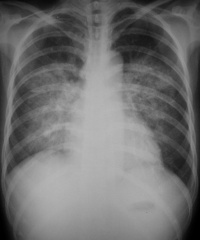

肺水肿间质期的X线表现主要为肺血管纹理模糊,增多,肺门阴影不清,肺透光度降低,肺小叶间隔增宽。两下肺肋膈角区可见与胸膜垂直横向走行的KerleyB线,偶见上肺呈弧形斜向肺门较KerleyB线长的KerleyA线。肺泡水肿主要表现为腺泡状致密阴影,呈不规则相互融合的模糊阴影,弥漫分布或局限于一侧或一叶,或从肺门两侧向外扩展逐渐变淡成典型的蝴蝶状阴影。有时可伴少量胸腔积液。但肺含量增加30%以上才可出现上述表现。CT和核磁共振成像术可定量甚至区分肺充血和肺间质水肿,但费用昂贵。

- 肺纹理和肺门阴影边缘模糊。

- 肺血重新分布现象,即由正常时上肺血管比下肺血管细变为上肺野血管增粗。

- 支气管袖口征,支气管轴位投影可见管壁环形厚度增宽,边缘模糊,称为袖口征。

- 间隔线阴影,其病理基础是小叶间隔水肿。可分为KerleyA、B、C线,以B线最常见,长度小于2cm,与胸膜垂直。

- 胸膜下水肿,类似胸膜增厚,不随体位改变而变化。叶间胸膜下水肿表现为叶间裂增厚。

- 常合并心影增大。可有少量胸水。